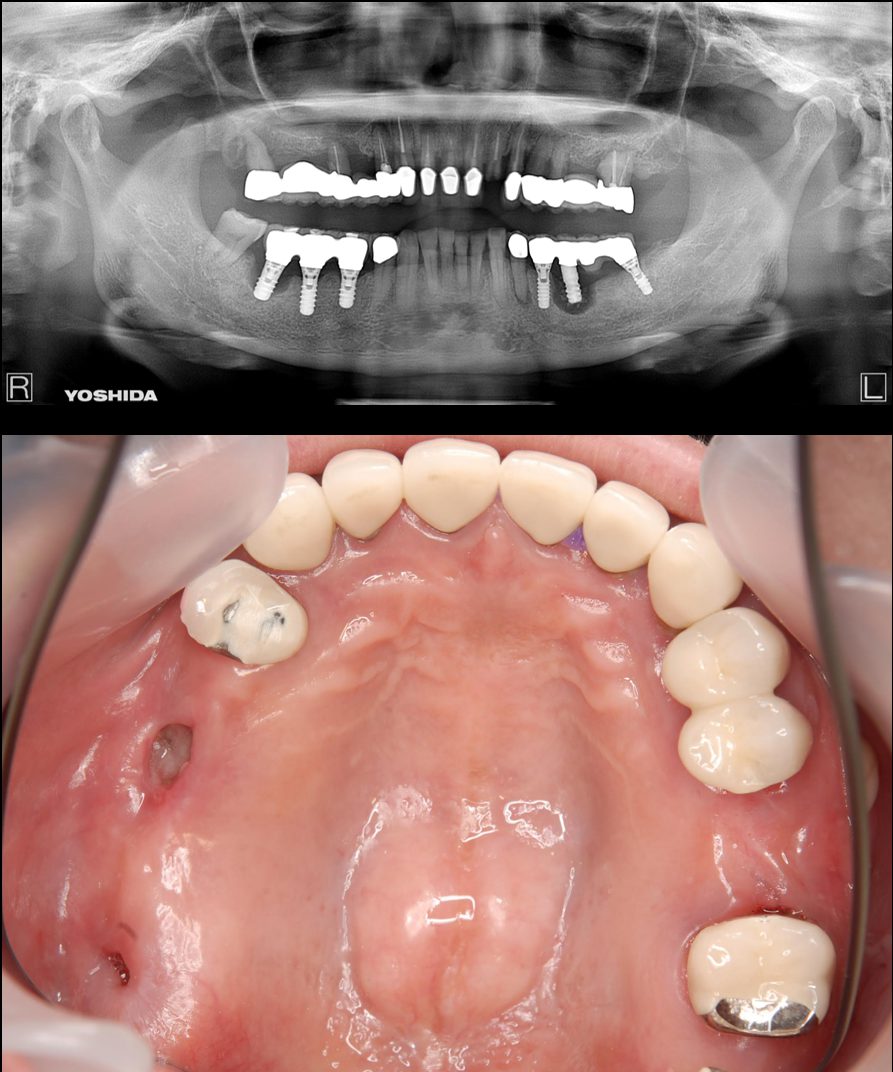

症例2【70代女性】主訴 義歯がわずらわしい・しっかり噛みたい

治療前

治療後(2年経過)

主訴 上顎のみ部分義歯を使用しているが、入れ歯が煩わしい、固定制のインプラントにして欲しいと来院。

左右上顎第一大臼歯相当は、骨の高さが不足しており、ソケットリフト(骨造成)の必要があり、左右第一小臼歯、第一大臼歯支台のインプラントブリッジを提案。

採血で得られた、CGFメンブレンとAFGブロック(人工骨β‐TCPとAFGを混ぜたブロック)を使用し骨を挙上し、インプラントを埋入。

右下のブリッジも、短根歯で動揺が激しい為に抜歯し、インプラント埋入。

上顎の免荷期間は約4ヶ月、下顎の免荷期間は約2ヶ月を経て、仮歯を装着、リハビリをし、メタルボンド(金属焼付ポーセレン)を装着。

費用 280万(オペ・ソケットリフト・人工骨・採血による濃縮血小板生成・仮歯・最終補綴物まで含む)